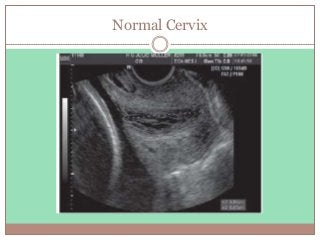

Normal Cervix

Low Risk (> 3.0 cm)

 LOW risk of preterm birth.

 FFN testing NOT mandatory.

 Observe for 4 to 6 hours to confirm fetal well-being.

 Reactive nonstress test

 Rule out abruption

 Rule out Infection.

 Rule out Cervical change

 Arrange follow-up in one to two weeks

 Give PTL instructions

 Bleeding, rupture of membranes, decreased fetal activity